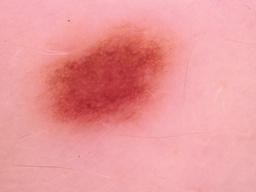

{

"age_approx": 35,

"anatom_site_general": "anterior torso",

"concomitant_biopsy": true,

"diagnosis_1": "Benign",

"diagnosis_2": "Benign melanocytic proliferations",

"diagnosis_3": "Nevus",

"diagnosis_confirm_type": "histopathology",

"image_type": "dermoscopic",

"lesion_id": "IL_6472749",

"melanocytic": true,

"sex": "female"